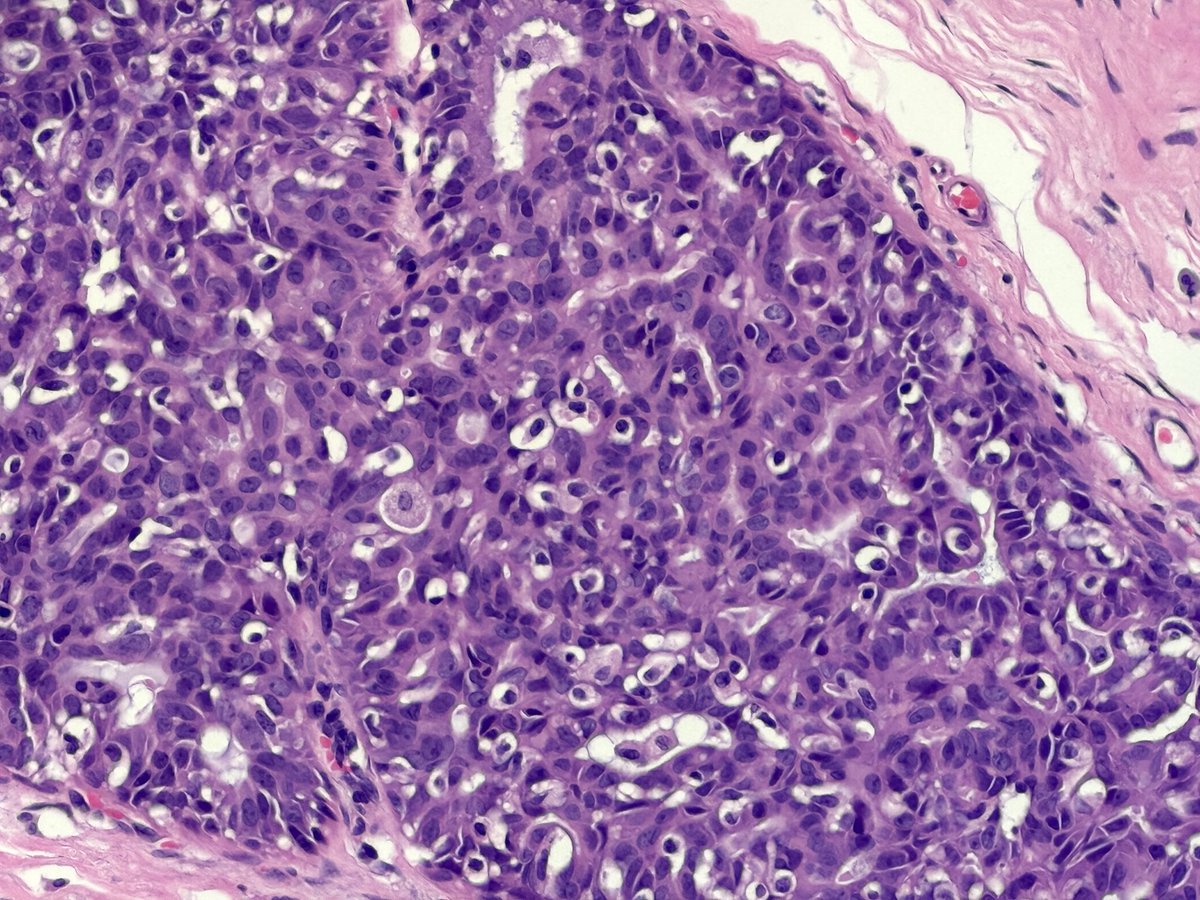

Thursday education day! A deceptive #BreastCarcinoma

#TubularCarcinoma

Well formed, single layered tubules.

CK5, SMMHC and p63 very helpful with internal neighbourhood controls positive.